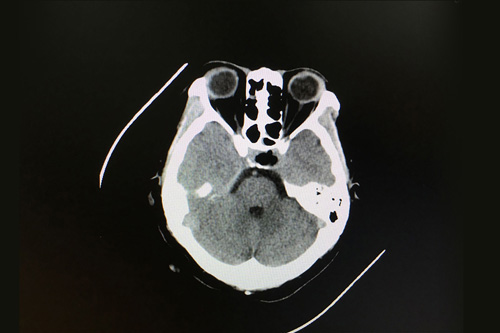

患者术后影像:鞍区肿瘤术后改变,脑内未见明显异常

手术后,患者恢复很快,仅在重症监护室待了一天就回到普通病房。术后第五天,患者的泌乳素水平仅高出参考值10个单位,正在慢慢接近正常,视物模糊,头痛头晕的症状也基本消失。